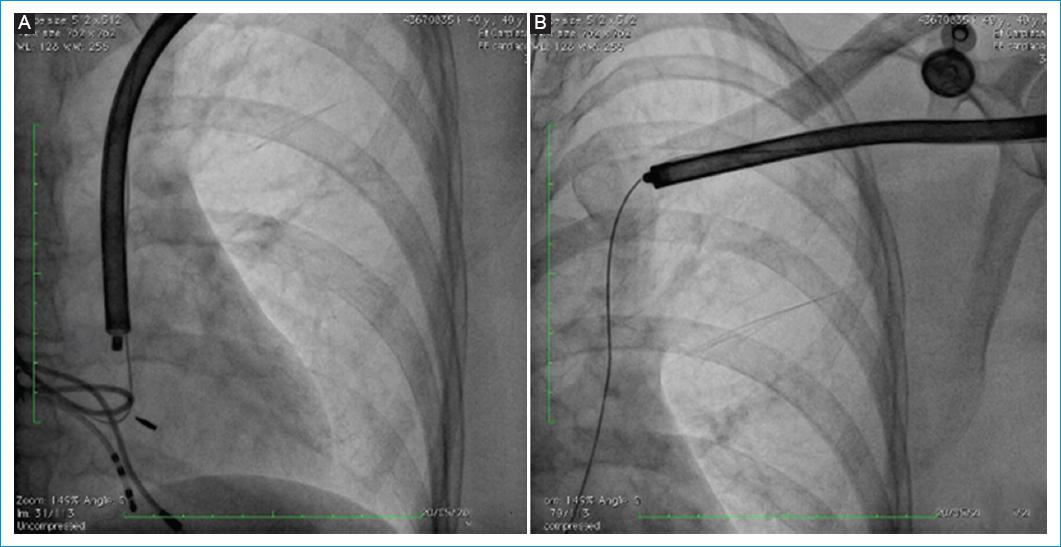

Bajo anestesia general se realizó punción de la vena femoral común derecha y a través de esta se posicionó catéter cuadripolar en el ápex del ventrículo derecho (Fig. 1). Luego, se realizó disección por planos anatómicos hasta la región subpectoral izquierda de donde se explantó el dispositivo y con ayuda de un electrobisturí se liberó el electrodo hasta la región infraclavicular izquierda, posición en la cual se realizó una sutura hemostática. Previa verificación de la integridad del lumen, se cortó el electrodo en la porción distal y a través del lumen se avanzó un Lead Locking Device (LLD) de Spectranetics® (Phillips, Colorado Springs, USA) y sobre este se avanzó vaina de corte rotacional mecánica TightRail 13 Fr de Spectranetics® hasta la porción más proximal del electrodo (pasando por la vena subclavia y la vena cava superior izquierda persistente) y con ayuda de contra-tracción se extrajo casi la totalidad del electrodo, dejando remanente menor de 1 cm (Fig. 2). Antes de retirar la vaina, se avanzó guía 0.032” de 1.5 m, y con técnica de guía retenida se realizó implante de marcapasos bicameral definitivo, sin documentarse estimulación diafragmática a máxima salida (Fig. 3). Debido a que los demás electrodos no estaban generando complicaciones de ningún tipo, no se intentó su extracción.

Figura 2 Imagen de retiro del dispositivo con Spectranetics®. A: proyección PA de hemitórax izquierdo. Se observa el dispositivo TightRail de Spectranepctranetics® siguiendo el trayecto del electrodo. B: proyección PA de hemitórax izquierdo. Se observa cómo se retira casi en la totalidad el electrodo; también se observa la guía que se usó para el nuevo implante.